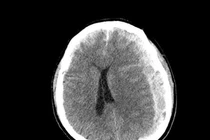

Hình ảnh tụ máu não dưới màng cứng khi nhập viện, trước phẫu thuật - Ảnh BVCC

Trước băn khoăn của gia đình, BS Huyền đã tư vấn ưu tiên chụp MRI sọ não. Kết quả chụp MRI sọ não cấp đã xác định người bệnh có khối tụ máu não dưới màng cứng mạn tính kích thước lớn vùng thái dương, gây hiệu ứng khối và đè đẩy đường giữa của não.

Đây là tình trạng đặc biệt nguy hiểm, bởi khối tụ máu có thể tiến triển âm thầm trong nhiều tuần với triệu chứng kín đáo như chậm chạp, giảm trí nhớ, rối loạn ngôn ngữ nhưng có nguy cơ cao dẫn đến liệt vận động, tụt kẹt não, hôn mê và tử vong nếu không được xử trí kịp thời.

Ngay sau khi có kết quả chẩn đoán hình ảnh, ông P.V.D được chuyển sang chuyên Khoa Phẫu thuật thần kinh sọ não để phẫu thuật cấp cứu lấy bỏ tụ máu, giải phóng chèn ép nhu mô não. Đồng thời, người bệnh được chỉ định điều trị thuốc kháng động kinh do đã có nhiều cơn co giật rõ ràng trước đó. Sau can thiệp, tình trạng ý thức cải thiện tốt, không xuất hiện cơn co giật.